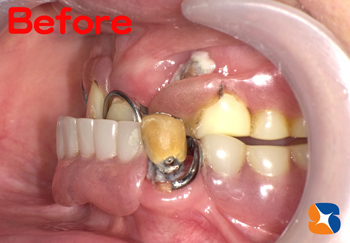

クリスマス日の朝、30代の自営の男性。主訴は「事故で前歯を損傷した。」とのこと。マイクロスコープ等で患部を精査すると差し歯の根が割れていることが判明しました。

抜歯の必要性を伝えたところ、「元々歯並びも悪かったので、前歯3本ともキレイにしたい。抜いた所はインプラントにする。」とのことでした。

お昼休みを使って、緊急手術を始める事になりました。

静脈麻酔鎮静法を使い、浅く眠った状態のまま治療を進めました。

抜歯した痕に自己採血を使って作った再生加工物(CGF)を添加しました。

歯茎を切らず、抜歯した痕に人工的なホールを設け、長さ18㍉のインプラントを移植しました。

また、抜歯した両サイドの2本の歯(1本は神経あり)を削って、オールセラミックの歯を入れる準備も行いました。